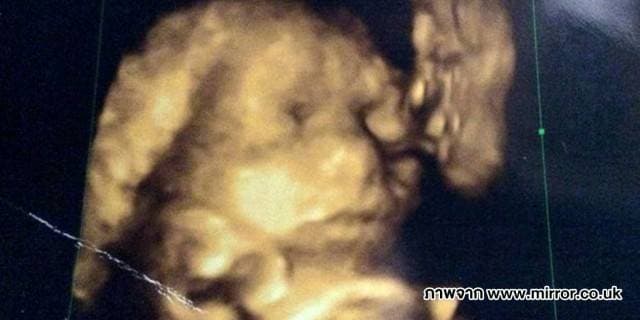

ข่าวอัพเดท : พบใบหน้าชายชราในภาพอัลตร้าซาวด์ครรภ

พบใบหน้าชายชราในภาพอัลตร้าซาวด์ครรภ์ของสาวท้องแก่